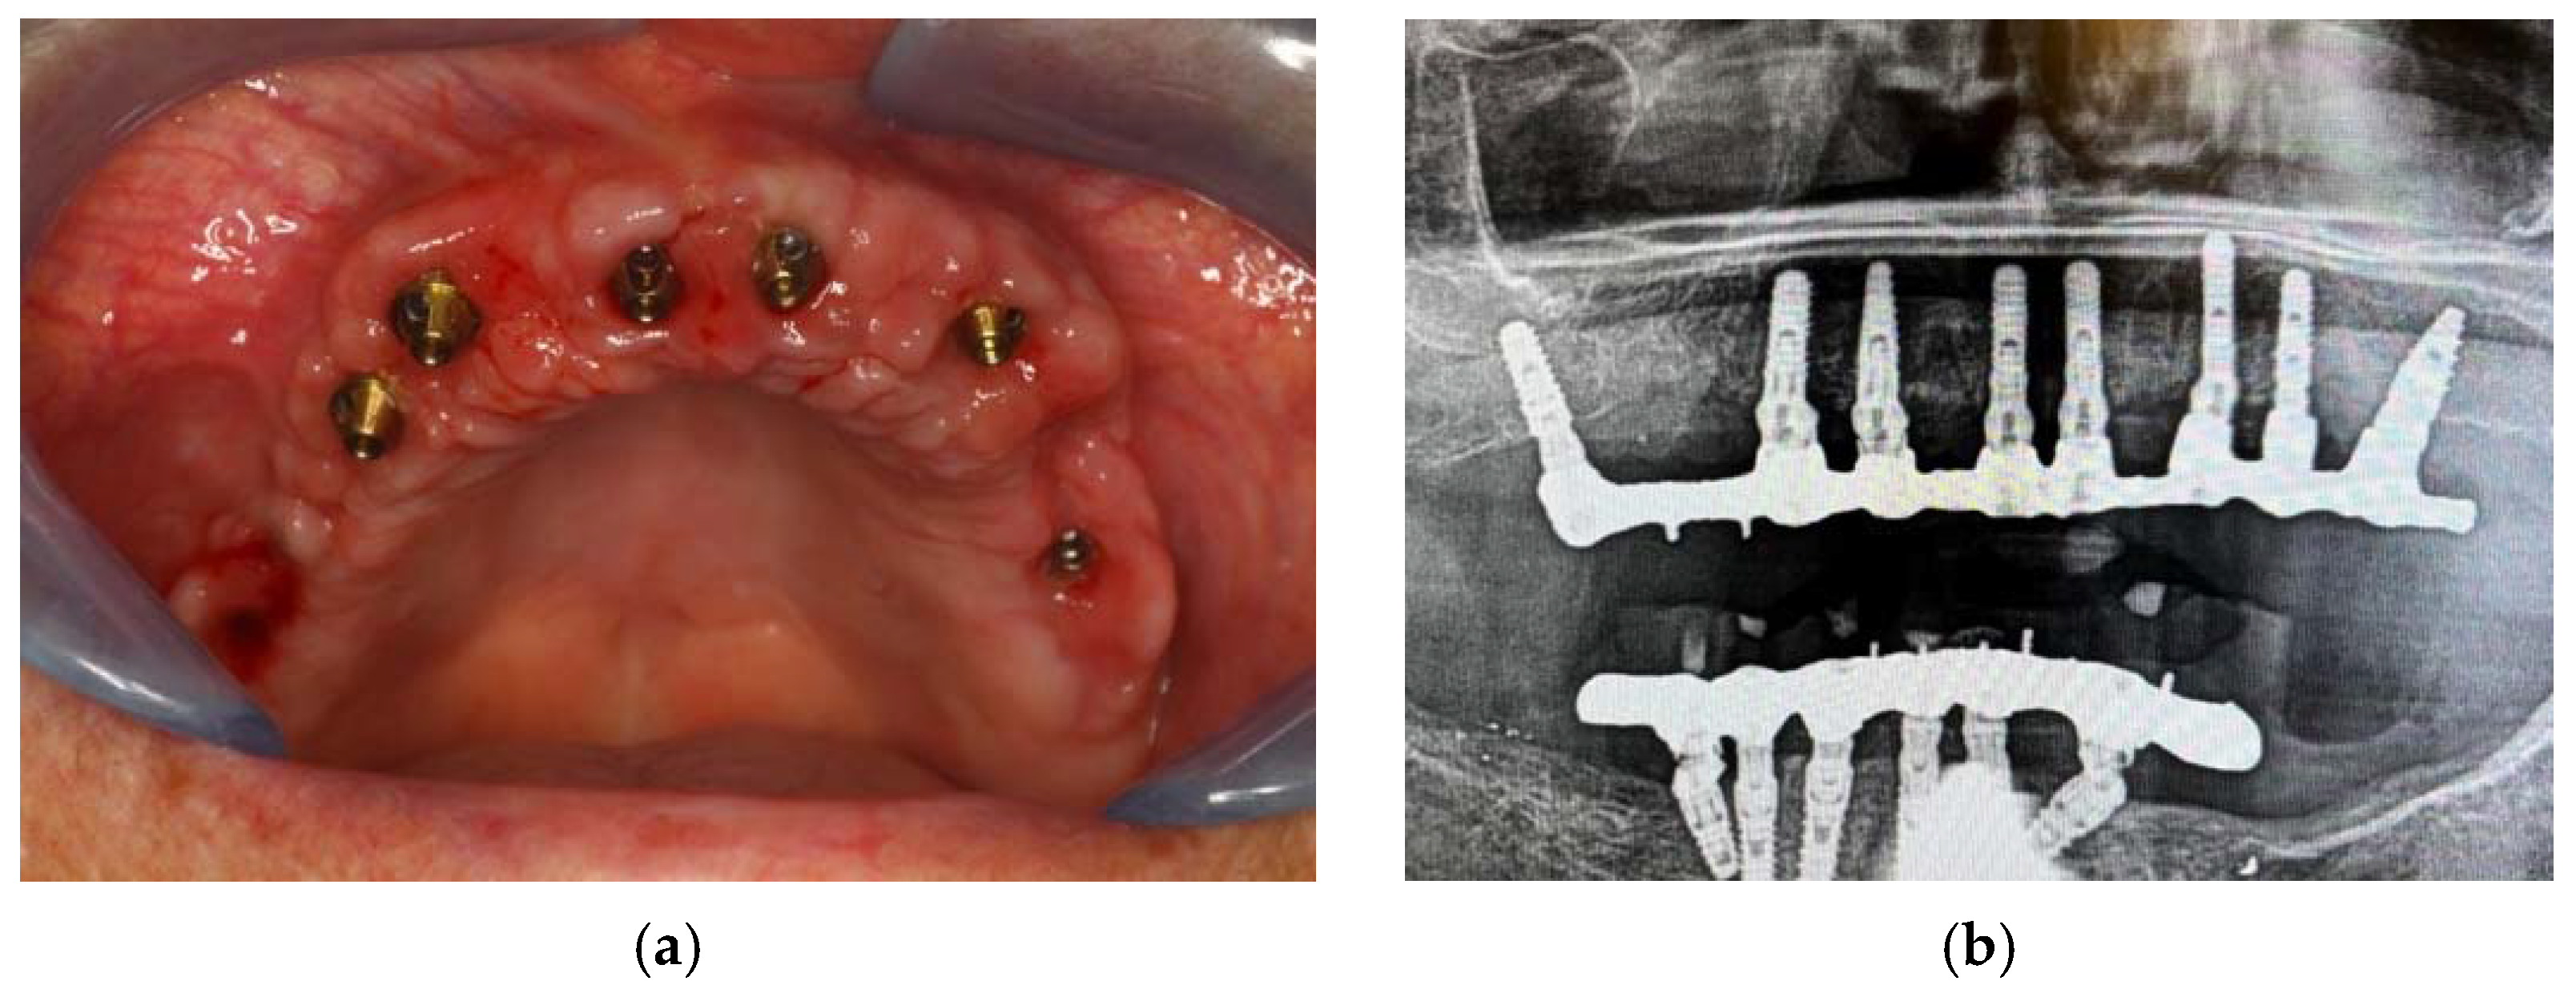

2. Materials, Methods and Results

Surgical Procedure